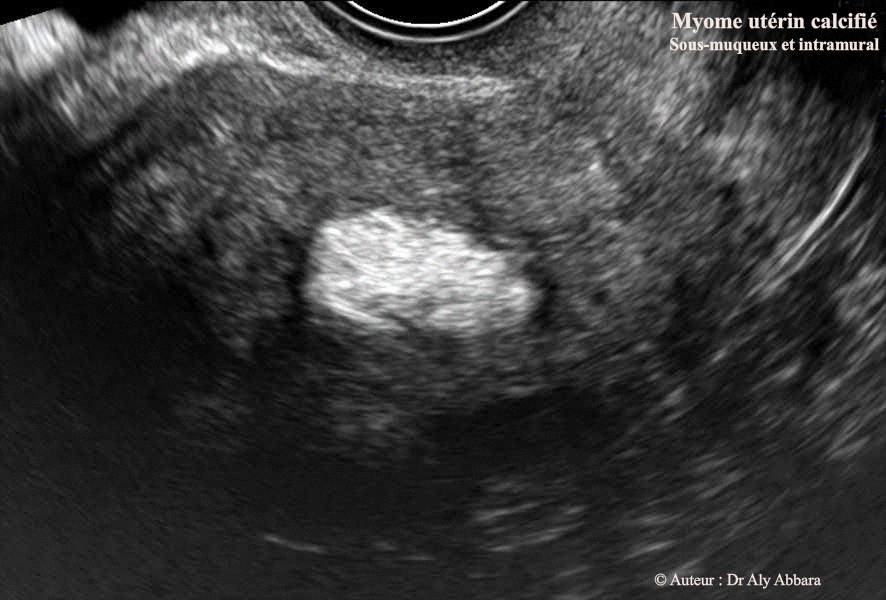

Myome calcifié endocavitaire utérin

Images échographiques animées montrant un fibrome utérin calcifié, sous-muqueux et

intramural (> 50%) = classe 2 ; de 19.2 x 18.6 x 10 mm de diamètre (environ 2 cm3)

Auteur : Dr Aly Abbara